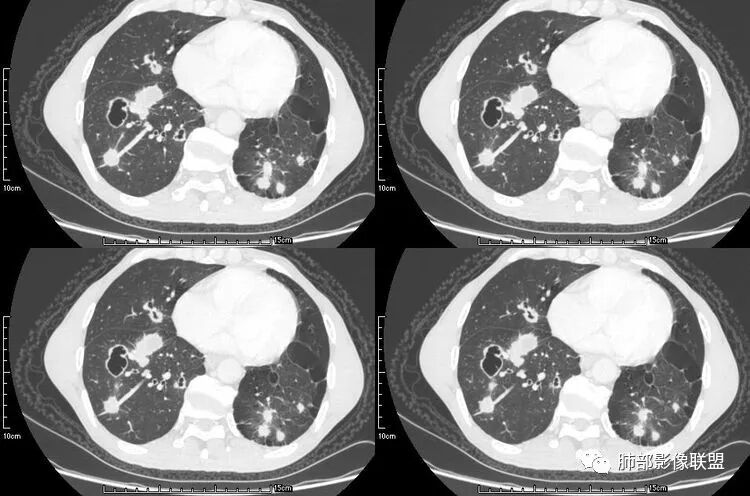

患者老年男性,咳嗽、咳痰、痰中带血伴胸闷2月余。长期大量吸烟史。查肝肾功能、血糖、血脂、心肌酶、电解质、血沉、C反应蛋白、抗“O”、类风湿因子、抗核抗体谱无明显异常。肿瘤标志物提示NSE、CYFRA21-1稍升高。胸部CT:肺气肿背景,左肺下叶后基底段不规则肿块影,见支气管截断,内见大片状低密度区及部分血管影,增强轻度强化,远端空洞形成。双肺多发不规则实性结节影、见毛刺、胸膜牵拉及血管集束,结节内见空洞形成,部分可见血管影,多位于胸膜下。双肺见多发肺大泡。综合考虑左下肺恶性病变并双肺转移。鳞癌或淋巴瘤可能。鉴别血管炎性病变及真菌感染。

左肺下叶团块病灶,有明显张力,增强后病灶内部有可疑延迟强化,看不清楚病灶与支气管的关系,应该支气管受压阻塞了,双肺多发胸膜下小结节,病灶小结节病灶有平行胸膜生长的表现,部分小结节厚壁,部分薄壁,,还有一部分有内容物,这需要两元论,左肺下叶肺癌(腺癌)伴转移,同时合并真菌感染。

张延军:双肺多发结节,空洞影,后者洞壁厚薄不均匀,部分腔内丝丝落落,呈分叶征,边缘见毛刺影,病灶大部分位于胸膜下,与血管相连,右肺下叶前基底段结节近段支气管截断,远端见空腔。左肺下叶病灶密度不均,背段支气管壁增厚,管腔狭窄。考虑1.双肺下叶占位性病变伴肺内空洞性转移 2.多原发的占位 3.肉芽肿性血管炎代排。

本病例左肺下叶肿块,有深分叶、毛刺、胸膜牵拉凹陷、支气管截断及纵隔内淋巴结肿大等征象,都均支持病灶为恶性,如腺癌,而且叶间裂的多发结节也提示是腺癌来源可能大;双肺多发结节、肿块,大部分病灶有分叶、毛刺及胸膜凹陷的恶性征象,与原发肿瘤本身的性质有关,所以应该与左肺下叶肿块同源,而且双肺多发病灶内空洞也具有多样性;